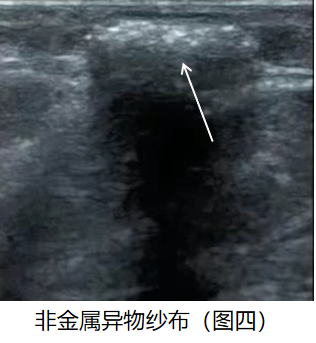

非金属异物如纱布等超声多表现为伤口后方组织内不规则形部分扭曲状强回声团,后方为大片宽带声影,如图四。